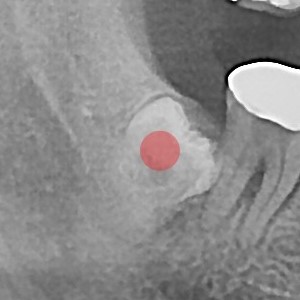

사랑니발치 30대/남성

ae27575af29d49719312fde5a1f0cca6_1764401898_7411.jpg